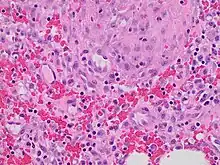

Granulation tissue is new connective tissue and microscopic blood vessels that form on the surfaces of a wound during the healing process.[1] Granulation tissue typically grows from the base of a wound and is able to fill wounds of almost any size. Examples of granulation tissue can be seen in pyogenic granulomas and pulp polyps. Its histological appearance is characterized by proliferation of fibroblasts and thin-walled, delicate capillaries (angiogenesis), and infiltrated inflammatory cells in a loose extracellular matrix.

The main immune cells active in the tissue are macrophages and neutrophils, although other leukocytes are also present. These work to phagocytize old or damaged tissue, and protect the healing tissue from pathogenic infection. This is necessary both to aid the healing process and to protect against invading pathogens, as the wound often does not have an effective skin barrier to act as a first line of defense.

It is necessary for a network of blood vessels to be established as soon as possible to provide the growing tissue with nutrients, to take away cellular wastes, and transport new leukocytes to the area. Fibroblasts, the main cells that deposit granulation tissue, depend on oxygen to proliferate and lay down the new extracellular matrix.

In vascularisation, also called angiogenesis, endothelial cells quickly grow into the tissue from older, intact blood vessels. These branch out in a systematic way, forming anastomoses with other vessels.